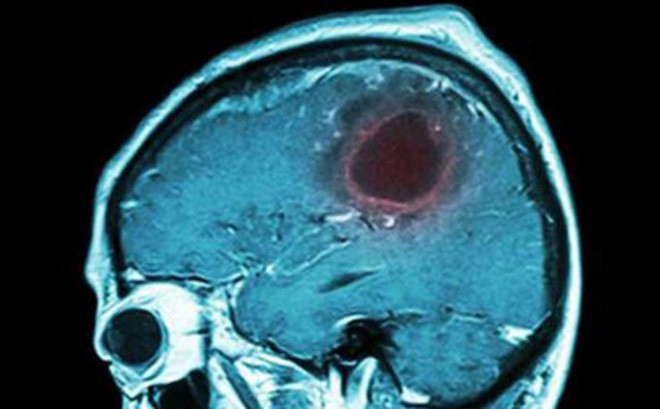

Hình ảnh u não qua phim chụp. Ảnh minh hoạ